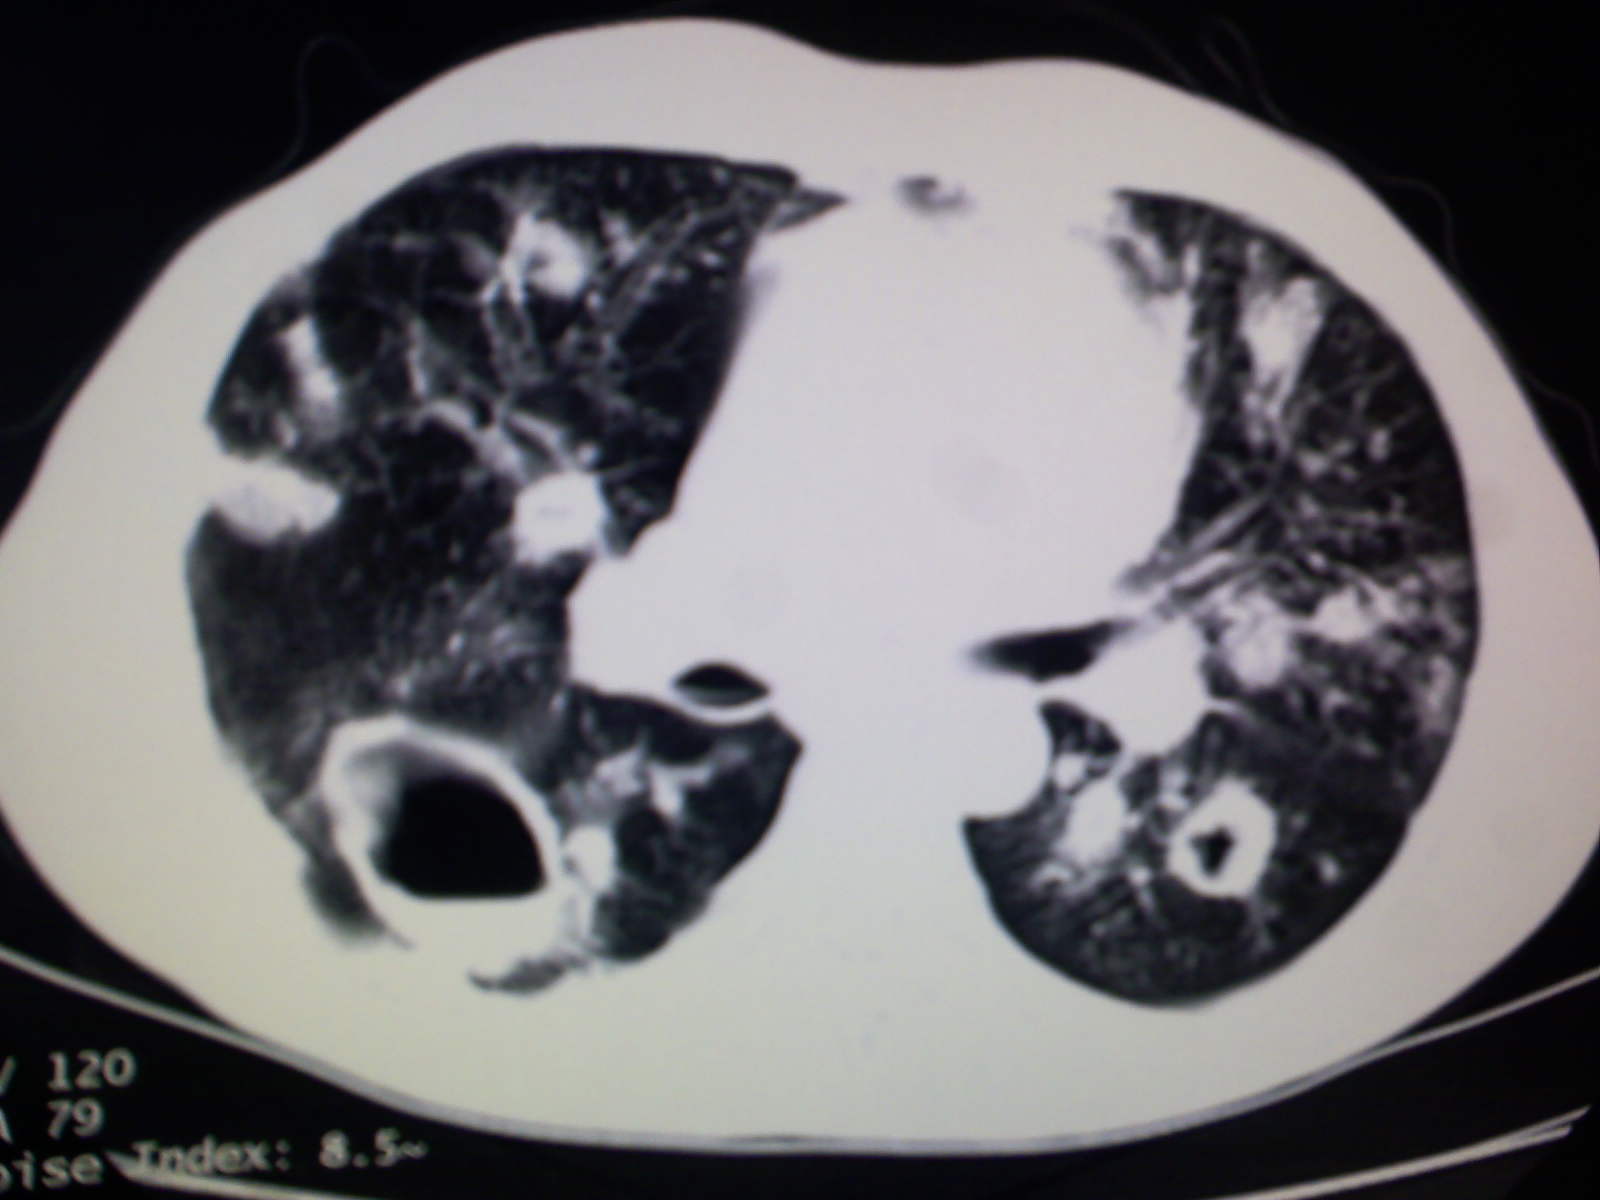

以下是引用卜一在2009-4-11 15:50:00的发言:[br]双肺继发性肺结核伴空洞形成,不排除合并霉菌感染!(病灶呈多形态 多特征 散在分布)。另:合并支气管扩张征伴感染!

以下是引用主力军在2009-4-11 15:55:00的发言:[br]两肺继发性肺结核可能性大。

以下是引用康鹏在2009-4-11 16:30:00的发言:[br]双肺继发性肺结核伴空洞形成合并感染[br]支气管扩张合并感染